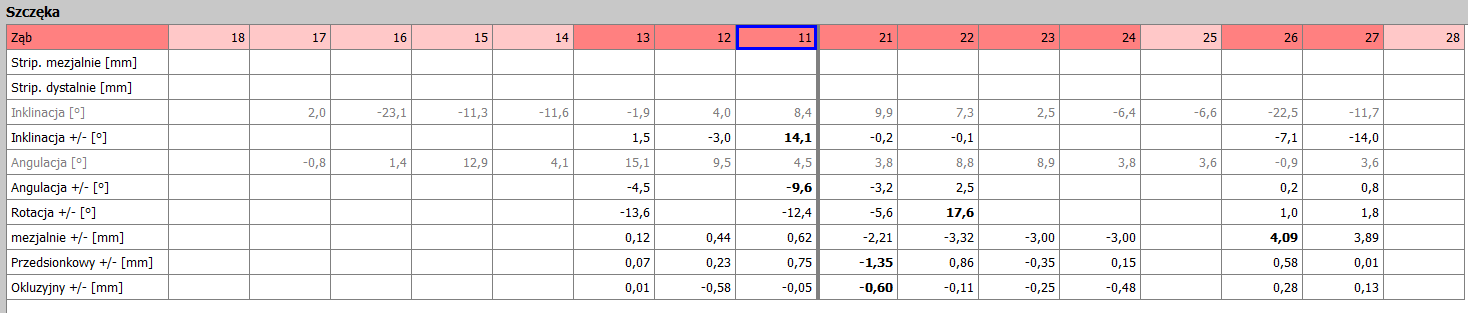

Analizę przemieszczeń zębów w zakresie mezjalizacji trzonowców w szczęce oraz przemieszczenie przedtrzonowca górnego rozpoczęto dopiero po uzupełnieniu zlecenia o analizę zdjęcia panoramicznego oraz badań dodatkowych. Opisano trzy opcje leczenia tego pacjenta. Pierwsza propozycja obejmowała brak mezjalizacji d. 26 i d.27; dystalizację w zakresie wybranych zębów. Druga propozycja obejmowała minimalną dystalizację drugiej ćwiartki łuku zębowego. Trzecia propozycja obejmowała sekwencyjną mezjalizację d. 26 oraz d. 27.

Cyfrowy plan leczenia przeanalizowano pod kątem osiągnięcia klinicznego celu zaplanowanego przez lekarza. Zaplanowana na cyfrowym planie leczenia mezjalizacja nie uwzględniała rekomendowanego sekwencyjnego przemieszczania zębów. Oznaczało to bardzo mało prawdopodobne zajście tych ruchów w jamie ustnej u pacjenta. Opisano lekarzowi, na czym polega sekwencyjna mezjalizacja zębów i jak zaprojektować ją w nowym planie leczenia. Zwrócono uwagę, że tego typu przemieszczenia zębów są bardzo wymagające, dlatego lekarze do zwiększenia możliwości ich zajścia stosują np. miniimplanty ortodontyczne. Opisano wpływ ilości i jakości attachmentów na zwiększenie przewidywalności ruchów zębowych.

- Zmodyfikować sekwencje mezjalizacji trzonowców.

- Plany leczenia dzielić na części, w których przemieszczane są pojedyncze zęby, a nie wszystkie zęby w maksymalnych zakresach jednocześnie.